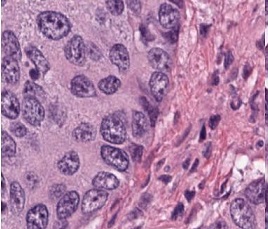

In the last few decades, the advent of computational pathology has catalyzed the advancements in clinical diagnosis, expedited development of new interactive models for pathology education and paved way for incredible rise in whole slide image analysis tools. It has revolutionized the entire tissue specimen analysis process for pathologists. From manually analyzing thousands of tissue slides via microscope requiring specialized doctors to automatic digital slide generation via scanning and using AI based deep learning techniques has spawned fatal disease diagnosis such as cancer using image analysis. In digital pathology nuclei and gland instance segmentation in whole slide images is of pivotal value for abnormality assessment. It plays a key role in histopathological image analyses whether it be identification of major chronic disease including tumor localization through segmentation or classification as benign or malignant. Glands are often considered as one of the main histological structures present in most of the organs as primary mechanism for proteins and carbohydrates secretion. However, it has been observed that adenocarcinomas, regarded as the most severe type of cancer, originates from glandular epithelium as malignant tumors. In figure 1, left patch shows histopathological image of a colon tissue stained with routinely used Haematoxylin and Eosin technique while right patch is individual gland of a colon tissue with sub structures. This makes understanding of glands morphology a pivotal step for assigning degree of malignancy of major adenocarcinomas e.g in breast, colon, lung and prostate. Thus accurate gland instance segmentation is considered as a necessary step for obtaining valid morphology information.